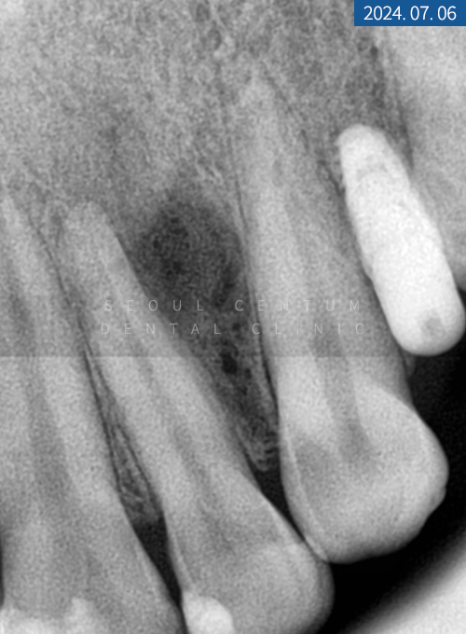

이번에 찾아오신 20대 환자분의 상태를 정확히 파악하기 위해 파노라마 엑스레이 촬영을 해보니 위턱과 아래턱 영구치 상실이 여러 군데 보였고 상악 전치부 부분 크랙이 심했습니다. 연령이 낮아 큰 골 소실은 없었지만 우측 상악 제1 소구치는 하방에 염증이 생겨 픽스처를 심는다면 GBR이 필요했는데요.

크랙도 범주가 크고 깊어 그대로 놔두게 되면 치수 감염과 하방 파절이 우려되어 조속한 대처가 필요했습니다.

진단

상실된 #14번은 합성골을 이식한 후 네이바이오텍 픽스처 직경 4.5mm, 높이 10mm로 이식하기로 했고 당일 좌측 상악 #15번 소구치도 동일한 브래드의 픽스처 4.0mm x 8.5mm 크기로 심기로 했습니다. 크랙이 심한 앞니와 측절치는 보철물을 수복해서 영구치를 보존하기로 했으며 크라운보다 치아 삭제량이 적고 심미적인 라미네이트를 부착하기로 했습니다.